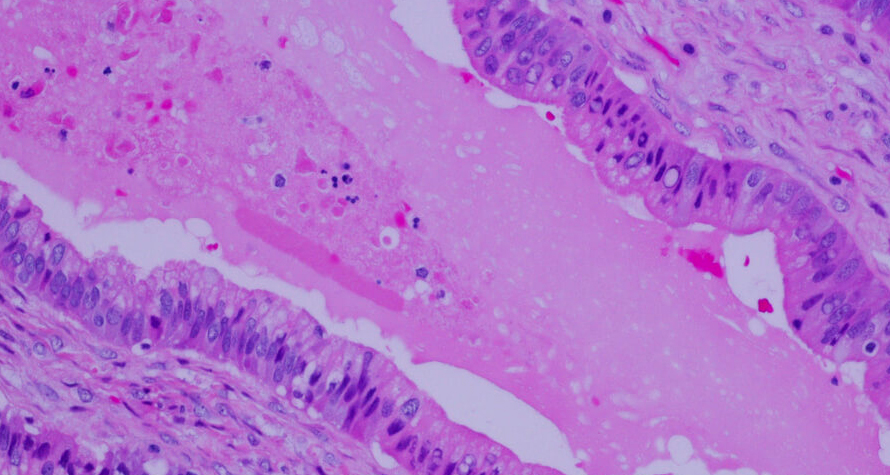

IKET is a Digital Pathologists Networking Platform where "knowledge" and "experience" are standardized for a sustainable report quality approach for all cases with a certain standardization and know-how.

What are the solutions by IKET

Access quickly to remote Digital Pathologist

IKET can provide you the digital pathology experienced pathologist you need, quickly through its remote Digital Pathologist Network.